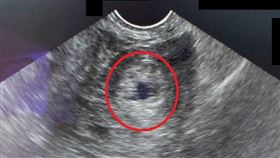

腹痛就醫 竟是罕見卵巢子宮外孕

一位37歲陳小姐因突然下腹痛、嘔吐、拉肚子到急診就醫...